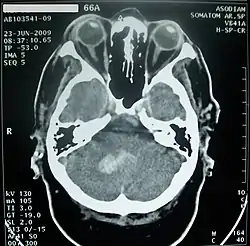

Нарушения мозгового кровообращения в мозжечке могут проходить либо по ишемическому (I63 согласно МКБ-10[39]), либо по геморрагическому (I61.4 согласно МКБ-10[39]) типу.

Инфаркт (нарушение кровообращения по ишемическому типу) мозжечка возникает при закупорке позвоночной, базилярной или мозжечковой артерий и при обширном поражении сопровождается выраженными общемозговыми симптомами, нарушением сознания, Закупорка передней нижней мозжечковой артерии приводит к инфаркту в области мозжечка и моста, что может вызвать головокружение, шум в ушах, тошноту на стороне поражения — парез мышц лица, мозжечковую атаксию, синдром Горнера. При закупорке верхней мозжечковой артерии чаще возникает головокружение, мозжечковая атаксия на стороне очага[44].

Кровоизлияние в мозжечок обычно проявляется головокружением, тошнотой и повторной рвотой при сохранении сознания. Больных часто беспокоит головная боль в затылочной области, у них обычно выявляются нистагм и атаксия в конечностях. При возникновении мозжечково-тенториального смещения или вклинении миндалин мозжечка в большое затылочное отверстие развивается нарушение сознания вплоть до комы, геми- или тетрапарез, поражения лицевого и отводящего нервов[44].